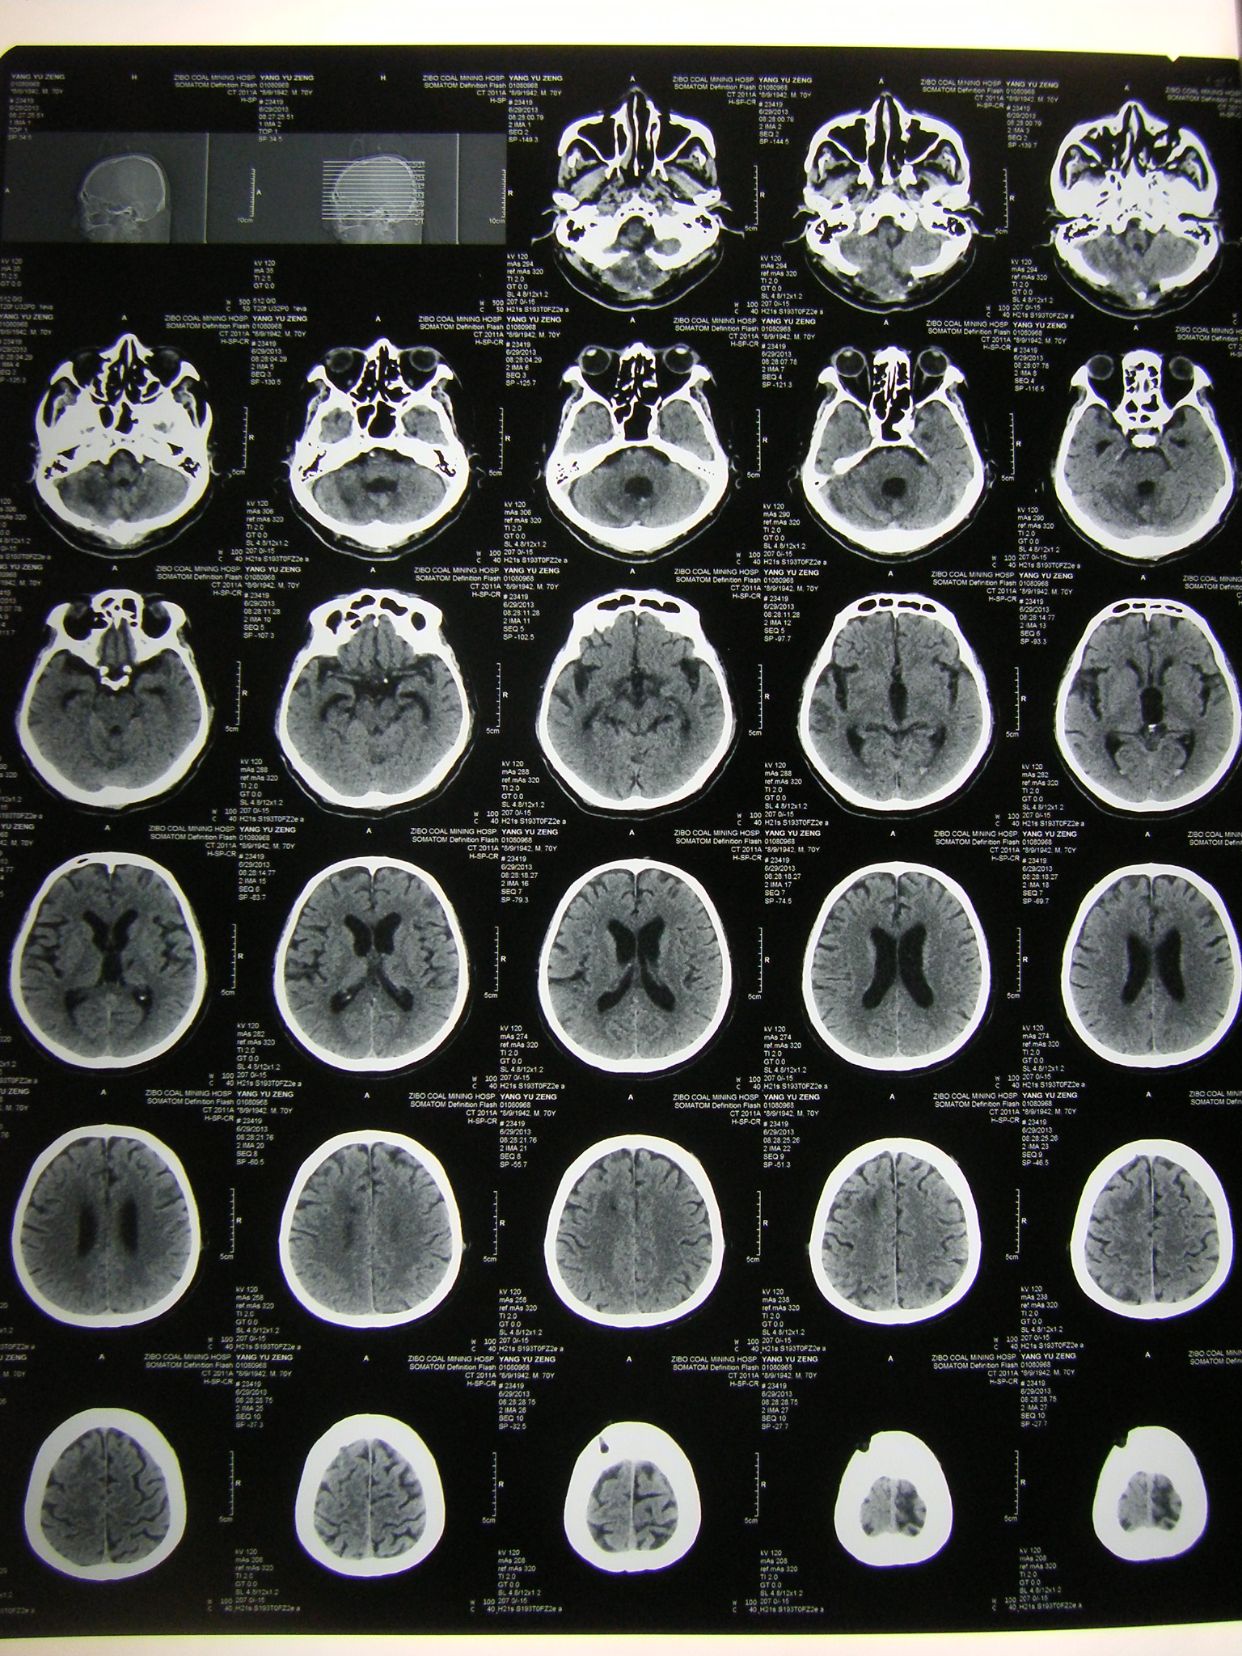

术后3天CT复查示,血肿清除满意,基底池四脑室可见。

术后四周CT复查,脑沟回清楚,无脑积水征象,患者神志清,四肢可遵嘱动作,出院康复。

术后1天CT复查示,血肿清除满意,基底池可见,患者刺激睁眼。

患者术后1月,神志清,正确回答问题,四肢话动良好,出院康复。